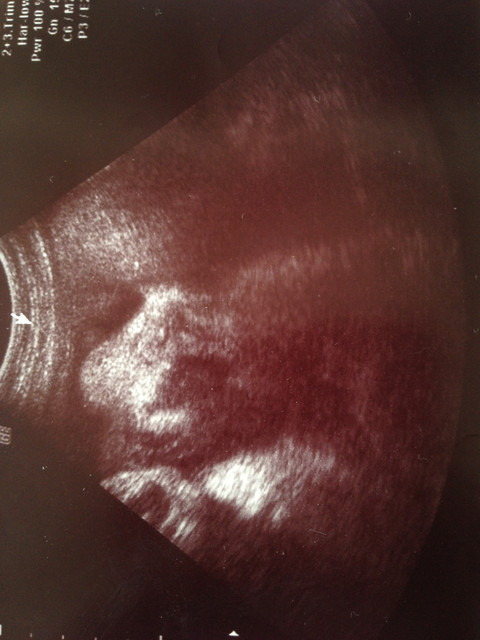

那在這邊就附上一張大大的照片吧

哇~整個輪廓好明顯哦~看起來是個可愛的娃娃呢~好期待與你相會!!!!